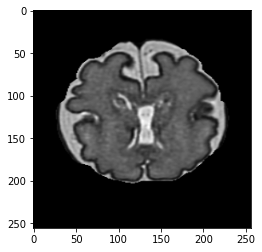

An image is converted into an intuitionistic fuzzy form, denoted as BIFSB^{IFS} to handle uncertainty in transition regions, thereby enabling better pixel classification. Image features are represented by membership, non-membership, and hesitation degrees. The CNNs for image classification utilise these intuitionistic fuzzy representations for improved feature extraction. The hesitation component highlights boundary regions, offering additional information for feature analysis. Higher hesitation values indicate more uncertainty, while zero hesitation reflects clear membership or non-membership. The membership and non-membership values define the degree of belonging or non-belonging for each pixel, and their distributions are illustrated in Fig.1.

Refer to caption

(a)

(b)

(c)

Figure 1: Intuitionistic fuzzy data in form of (a): membership, (b): non-membership and (c): hesitation degree.